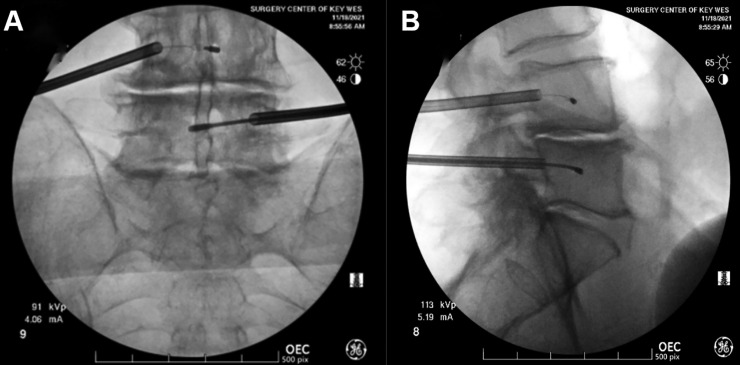

3. Transpedicular approach: A curved introducer is advanced through the pedicle into the vertebral body under fluoroscopic guidance

4. RF probe deployment: The probe is deployed to the midline of the vertebral body where the BVN is located

Transpedicular Approach:

• The introducer needle (typically 8G) enters at the superior-lateral aspect of the pedicle and advances toward the inferior-medial aspect

• Frequent alternating between true AP and true lateral imaging is essential to avoid breaching the pedicle cortex

• Goal: reach the posterior vertebral body in the lateral view before reaching the medial or inferior pedicle walls in the AP view